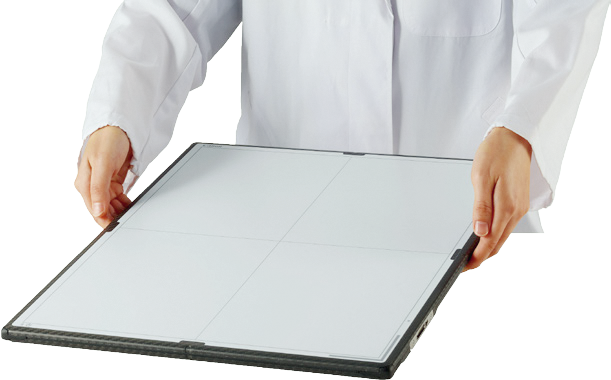

Bessere Bildgebung und bessere Diagnosen beginnen mit Canon CXDI. Jedes Canon DR-System zeigt die ausserordentliche Qualität und Zuverlässigkeit des Weltmarktführers.

Digitales Röntgen (Canon DR)

Canon CXDI-810CW / 710CW / 410CW

Mobile Detektoren mit Autodetect und höchster Dosisempfindlichkeit.

Canon CXDI-RF B1 Detektor

Mobiler Detektor für statische, dynamische und freie Aufnahmen